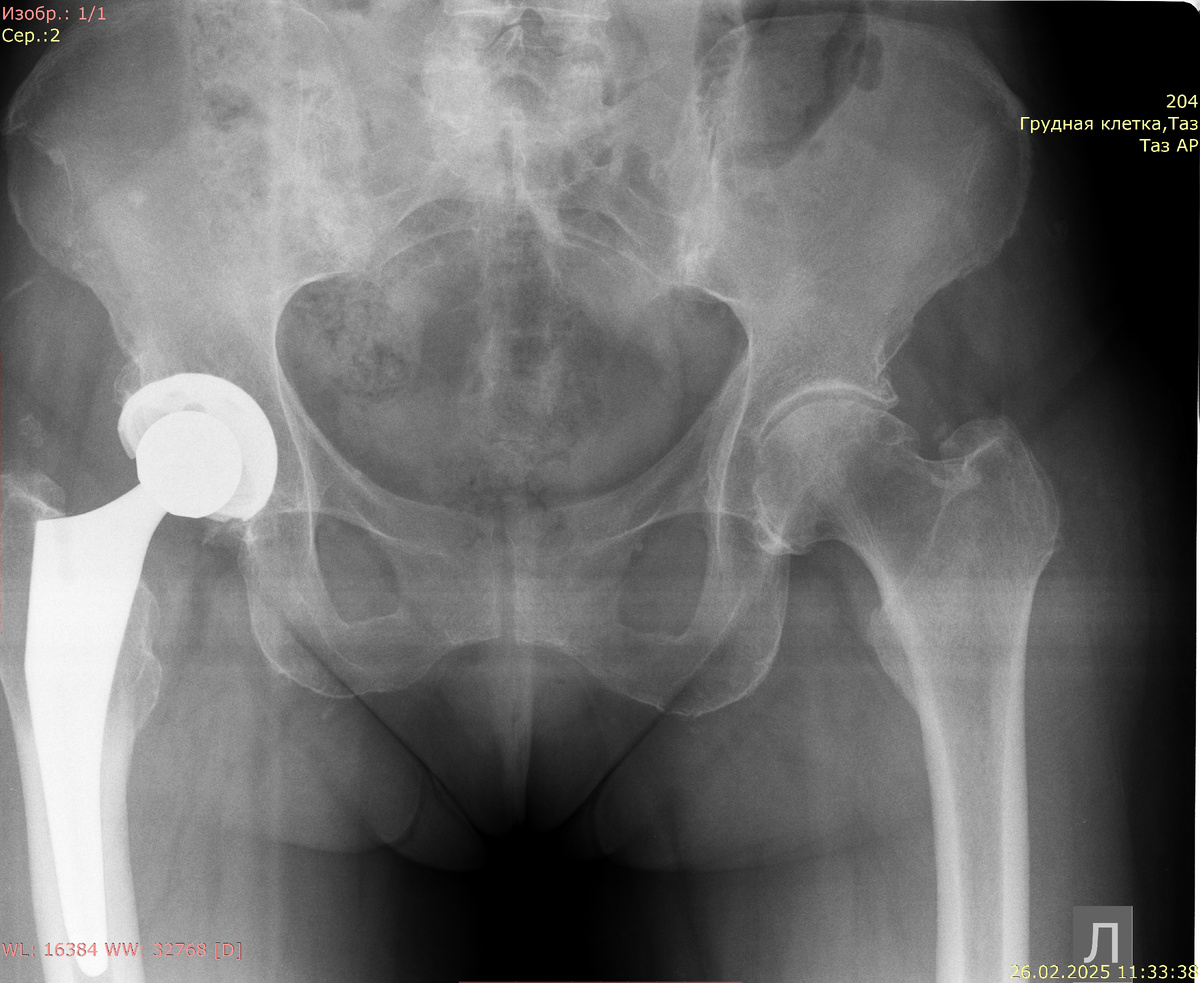

Рентгенография обоих тазобедренных суставов в прямой проекции:

Тотальное эндопротезирование правого тазобедренного сустава. Суставные поверхности эндопротеза конгруэнтны, головка эндопротеза центрирована в суставной впадине. Тазовый компонент металлический, положение его удовлетворительное, зон костной резорбции вокруг него не определяется. Бедренный компонент: расположение ножки эндопротеза в костномозговом канале нейтральное. Костно-деструктивных и костно-травматических изменений не выявлено. В окружающих мягких тканях зон патологической плотности не выявлено.

Суставные поверхности тазобедренного сустава конгруэнтны, головка бедренной кости центрирована в суставной впадине. Головка бедренной кости обычной формы и структуры. Шейка бедренной кости не укорочена, шеечно-диафизарный угол в пределах нормальных показателей. Вертлужная впадина обычной формы и структуры, склерозирована. Суставная щель в тазобедренном суставе сужена с минимальным значением от 0 до 3 мм. Суставные поверхности уплотнены, в субхондральном слое остеосклероз. Оссификаты по краю суставных поверхностей. Параартикулярные ткани без патологических рентгенопозитивных включений. Костно-деструктивных и костно-травматических изменений не выявлено.

Заключение: тотальное эндопротезирование правого тазобедренного сустава. Расположение и взаимоотношение компонентов эндопротеза удовлетворительное. Левосторонний коксартроз III-IV степени по Келлгрену-Лоуренсу.